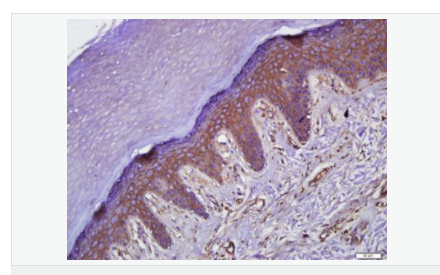

| 產品應用 | WB=1:500-2000 ELISA=1:5000-10000 IHC-P=1:100-500 IHC-F=1:100-500 Flow-Cyt=1μg/Test ICC=1:100 IF=1:100-500 (石蠟切片需做抗原修復) not yet tested in other applications. optimal dilutions/concentrations should be determined by the end user. |

| 產品介紹 | This gene encodes an integral membrane protein which is located at tight junctions. This protein may be involved in the formation and maintenance of the tight junction. The possibility of several alternatively spliced products has been suggested but the full nature of these products has not been described. [provided by RefSeq]. Function: May play a role in the formation and regulation of the tight junction (TJ) paracellular permeability barrier. Subunit: Interacts with TJP1/ZO1 and with VAPA. Subcellular Location: Membrane; Multi-pass membrane protein. Cell junction, tight junction. Tissue Specificity: Localized at tight junctions of both epithelial and endothelial cells. Highly expressed in kidney. Not detected in testis. Post-translational modifications: Phosphorylated upon DNA damage, probably by ATM or ATR. Dephosphorylated by PTPRJ. May be phosphorylated by PKC during translocation to cell-cell contacts. Similarity: Belongs to the ELL/occludin family. Contains 1 MARVEL domain. SWISS: Q16625 Gene ID: 100506658 Database links: Entrez Gene: 18260 Mouse Entrez Gene: 100506658 Human Omim: 602876 Human SwissProt: Q16625 Human SwissProt: Q61146 Mouse Unigene: 592605 Human Unigene: 4807 Mouse Unigene: 31429 Rat Important Note: This product as supplied is intended for research use only, not for use in human, therapeutic or diagnostic applications. |